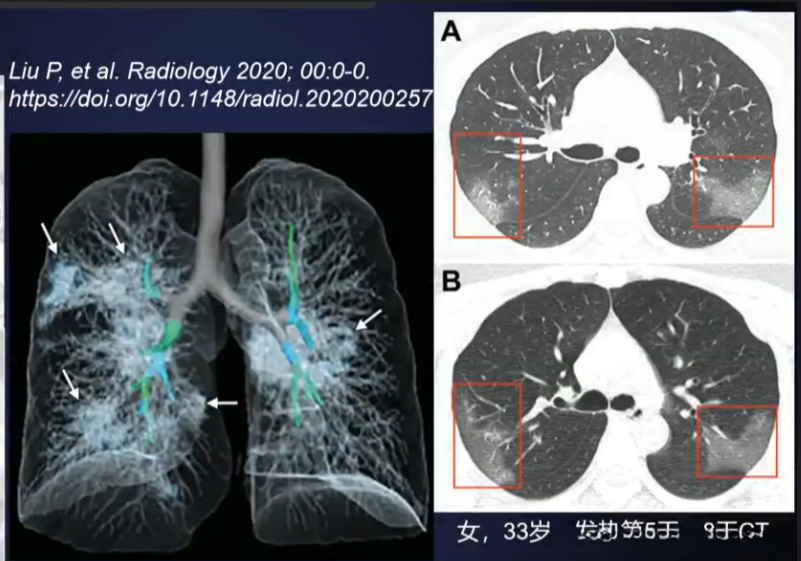

- 早期:病变局限;胸膜下/支气管血管束分布;结节斑片状GGO,其内血管影、间隔增厚

- 进展:病灶增多,范围扩大;铺路石征明显,磨玻璃影与时变共存;局部结构扭曲,支气管扩张